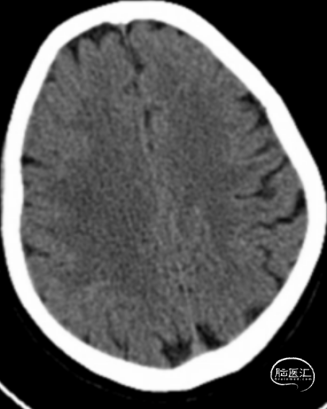

术前影像

术前CTA+CTP示:1.右侧大脑中动脉M1段闭塞,前交通开放,右侧后交通开放;2.右侧大脑中动脉供血区大面积TTP、MTT延长,CBF降低,CBV减低。

术前头颅CT示:颅内未见明显异常。